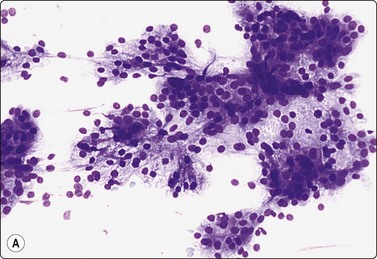

Sialadenitis (Figs 4.25, 4.26)

image image

Fig. 4.25 Chronic sialadenitis

Fragments of epithelium mainly of ductal origin showing mild reactive atypia and some squamous metaplasia; fragments of fibrous stroma; relatively few chronic inflammatory cells. (A, MGG, IP; (B, Pap, IP).

Fig. 4.26 Chronic sialadenitis

(A) Sheet of ductal epithelium showing squamous metaplasia. This could be mistaken for low-grade mucoepidermoid carcinoma or other low-grade neoplasm (Pap, HP); (B) Corresponding histology, most acinar epithelium replaced by fibrous tissue with patchy inflammatory cell infiltration, and prominent ducts showing mild reactive atypia and squamous metaplasia (H&E, IP).

Criteria for diagnosis

Purulent aspirate in acute, infective sialadenitis,

Scanty material of mainly ductal epithelial cells, few acinar cells in chronic sialadenitis,

Sheets of ductal epithelium showing regenerative atypia and/or squamous metaplasia,

Variable numbers of inflammatory cells, usually few in chronic sialadenitis,

Fragments of fibrous stroma.

Purulent material aspirated from a tender, swollen gland suggests infective sialadenitis. Smears contain a mixed population of numerous neutrophils, foamy degenerate cells and endothelial cells. The swelling should subside after antiinflammatory treatment.

Most cases of chronic sialadenitis referred for FNB are in a late stage when interstitial fibrosis and atrophy of acinar tissue have taken place. The inflammatory cell infiltration may have subsided and may be sparse and patchy. FNB smears are therefore often scanty, mainly of ductal epithelial cells associated with only few acinar cells and inconspicuous inflammatory cells. Fragments of fibrous stroma are often present (Fig. 4.25). Crystalloids may be present in the aspirate.95 Regenerating ductal epithelium in chronic sialadenitis may undergo squamous metaplasia and may appear atypical (Fig. 4.26). Mucus-like material from dilated ducts may be present. This may be suggestive of a neoplastic lesion or even of malignancy, mainly low-grade mucoepidermoid tumor. Multiple sampling and clinical correlation usually solves the problem.